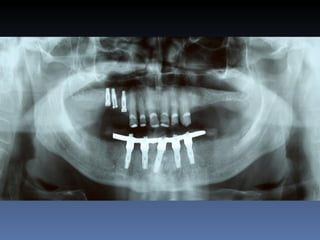

BOX 2

Silvia Maria Cardoso

Idade – 40 anos

Sexo – Feminino

Raça – Caucasiana

ASA – II

Data- 24-04-2012

Diagnóstico: Desdentada pré-maxila

Plano de tratamento:        Reabilitação com 2 blocos

“onlay” provenientes de Ilíaco fresco-congelado

(FFB); e posterior reabilitação protética fixa .